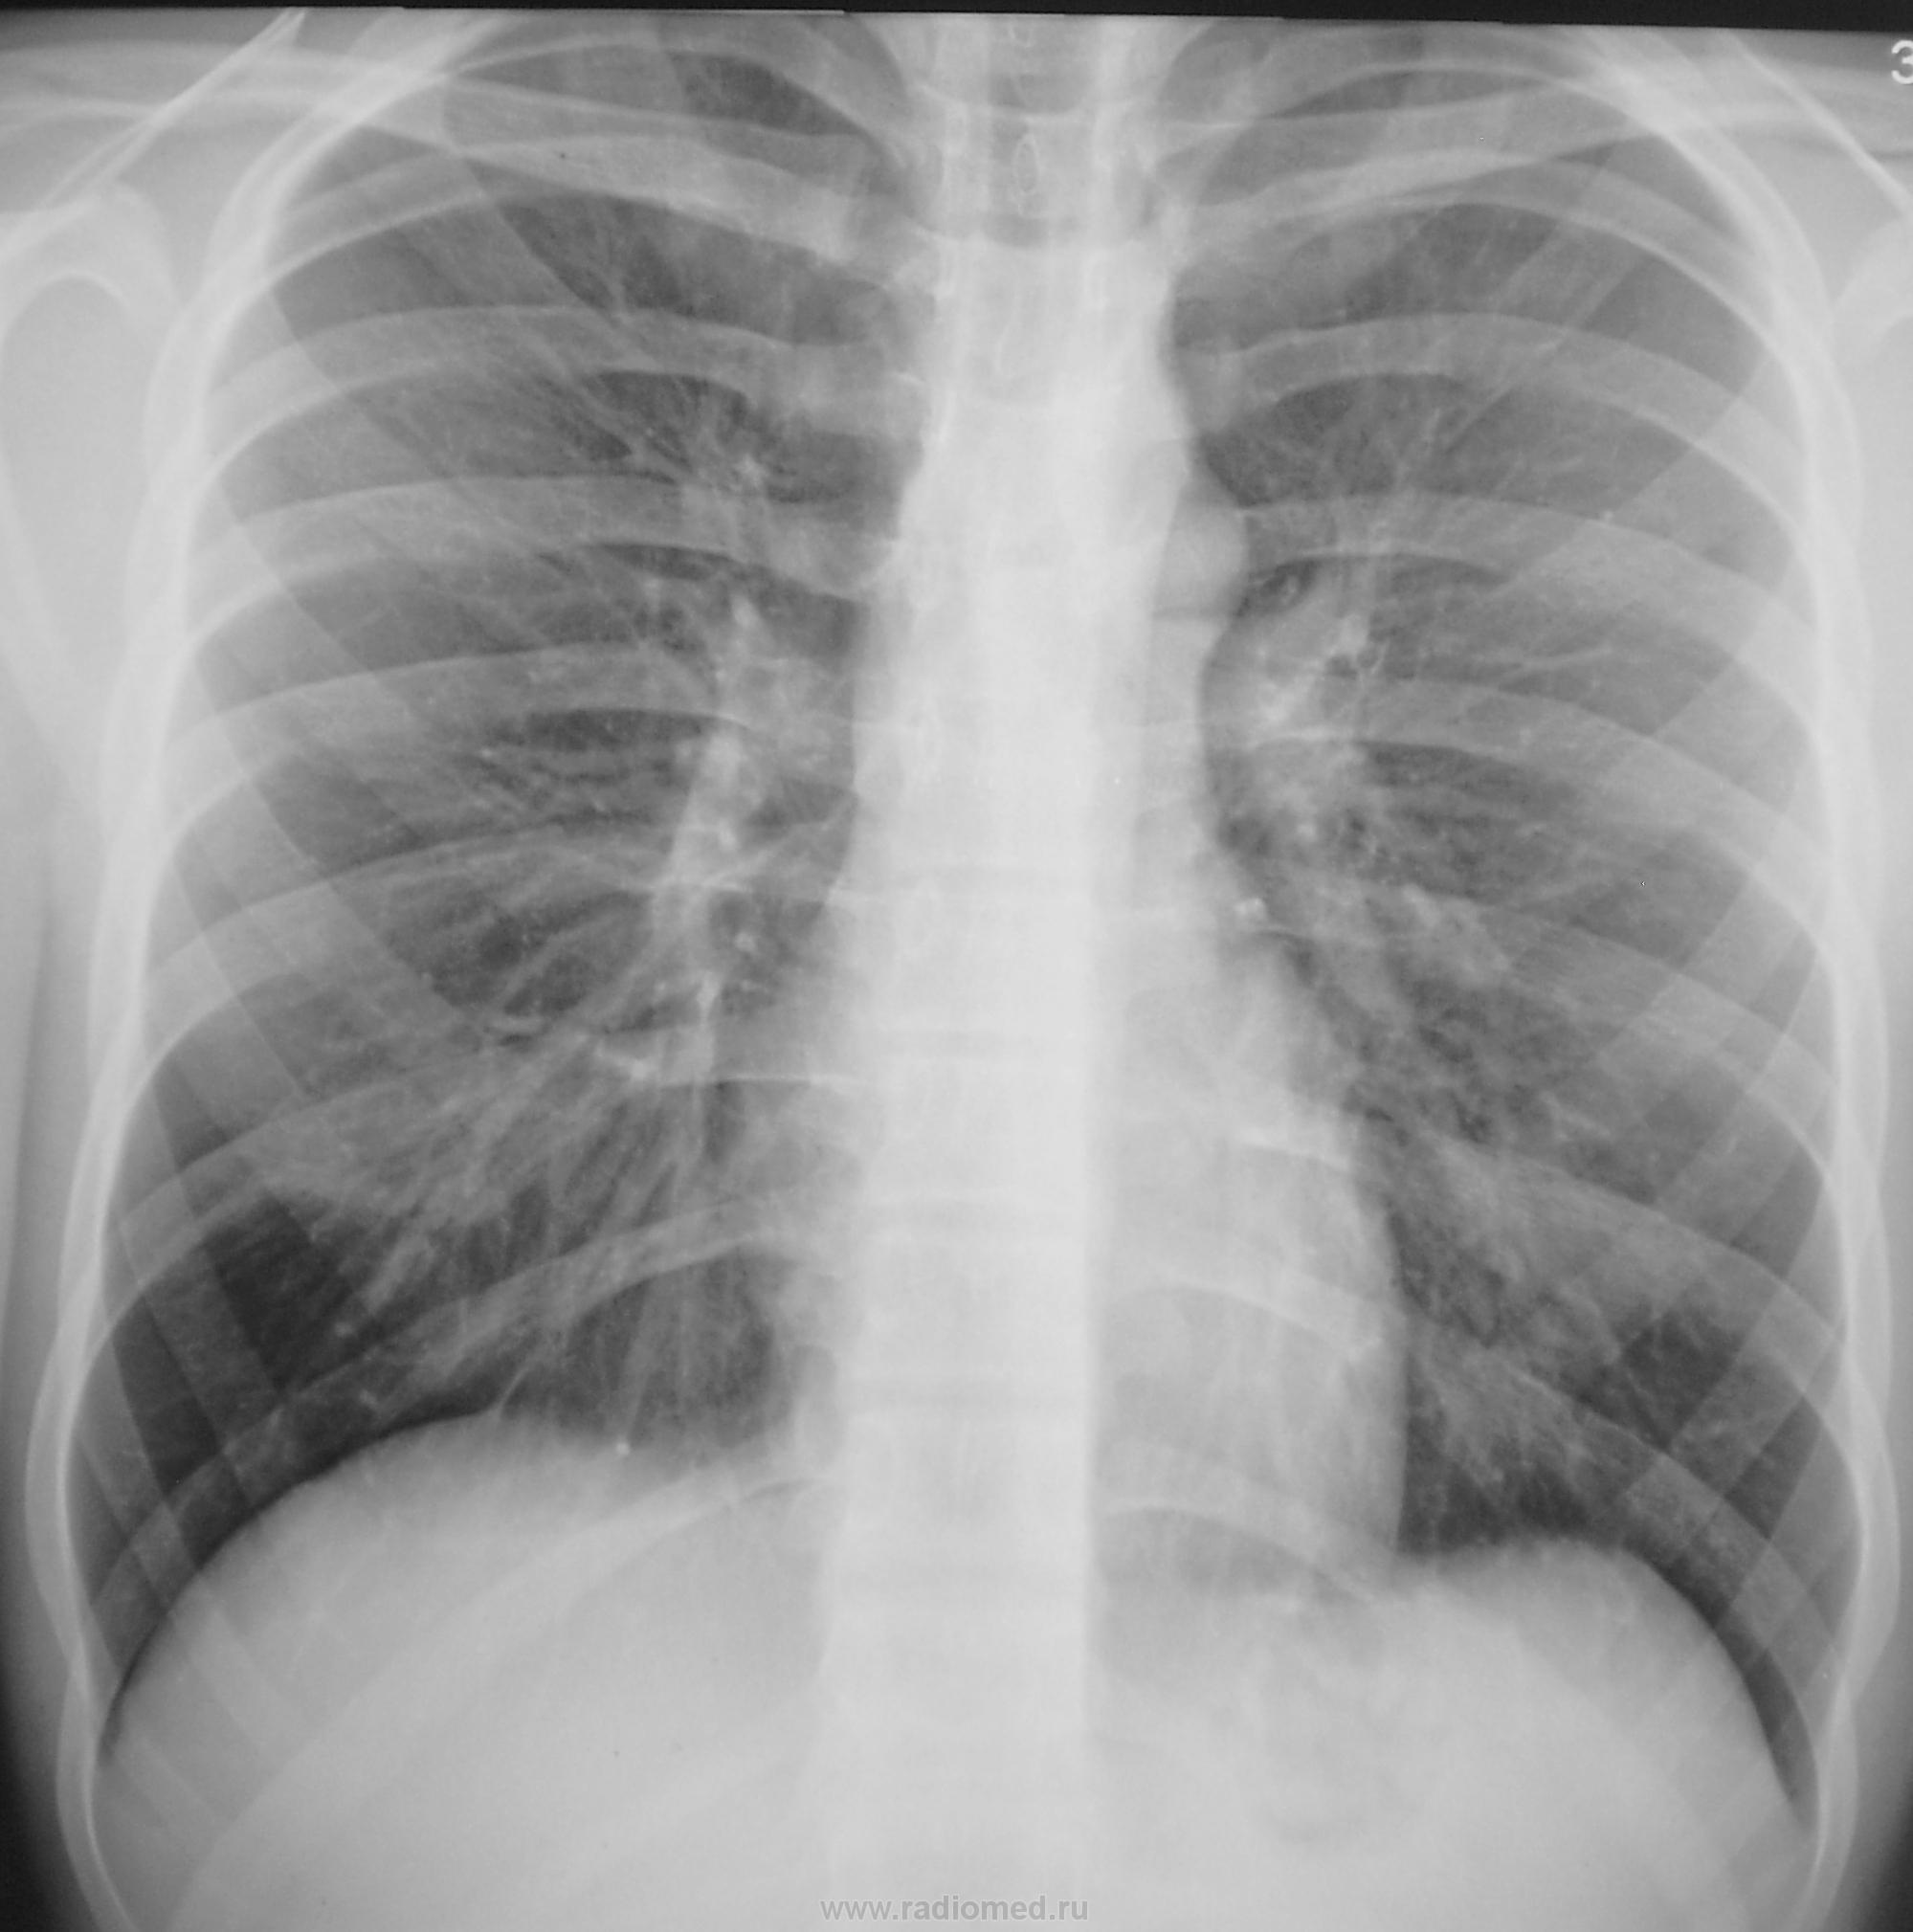

Произведена рентгенограмма в прямой проекции.

Смотрите рисунок.  Заключение написано на снимке. Кроме очагов в легких, имеется увеличение паратрахеального лимфатического узла. В ПТД на лечение.  Nikolas

Заключение написано на снимке. Кроме очагов в легких, имеется увеличение паратрахеального лимфатического узла. В ПТД на лечение.  Nikolas

Дело в том, что этого пациента я зацепил еще год тому назад.

Снимки ниже.